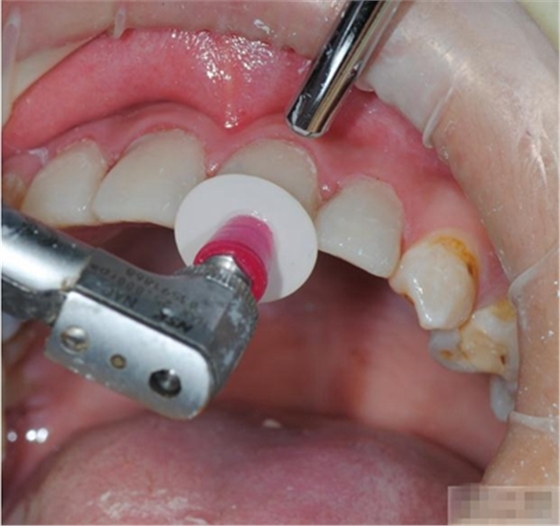

最先選擇最粗的拋光碟去除多余的充填物 建立最初的解剖形態(tài). 10,000 rpm

更換下一個(gè)拋光碟時(shí)要沖洗并吹干牙齒表面

使用中粗的拋光碟進(jìn)一步修整外形,建立邊緣脊和切邊. 10,000 rpm

更換下一個(gè)拋光碟時(shí)要沖洗并吹干牙齒表面.

選擇細(xì)的拋光碟進(jìn)行更進(jìn)一步的表面處理,并為最后的拋光準(zhǔn)備

用超細(xì)拋光碟進(jìn)行最終的拋光,最后完成的表面非常光潔,并且能夠保持很久。

30,000 rpm